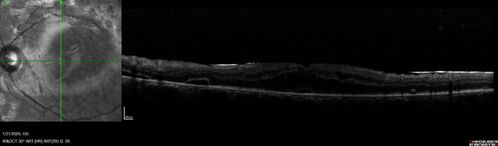

Severe diabetic tractional retinal detachment one year following diagnosis of type II Diabetes Mellitus

44 year old man The vision in the left eye started to decline about 4 days ago.  Prior to that the left eye was the better eye.  He was diagnosed with diabetes a year ago.

VA OD: Dcc20/50-1 OS: Dcc20/125-2, TP: OD:12 OS:13

Following two surgeries in each eye, silicone oil remaining forever, monthly anti-VEGF for severe DME - BCVA OU 20/200 at 3 years